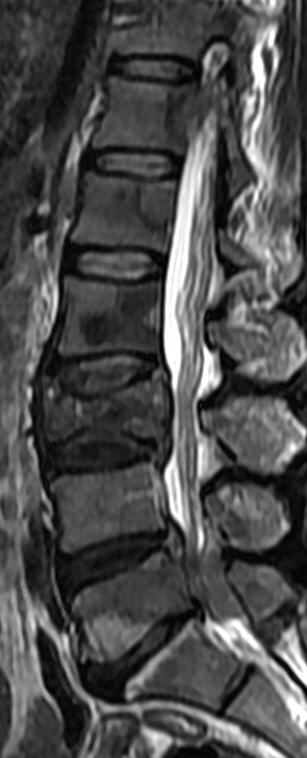

MRI

可提供腰椎管的矢状面、冠状面和轴位横断面上的影像。椎管狭窄以T2加权像显示较好,脑脊液为高信号,产生所谓“脊髓造影”的效果,而骨质增生,骨赘、间盘均为低信号,能清晰地显示椎管狭窄,以及对脊髓的压迫情况。但对肥大的黄韧带、骨质增生等的判断则不如较高清晰度CT扫描。

腰椎正常MRI解剖。

腰椎管狭窄MRI表现。